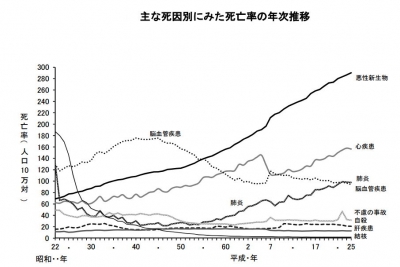

歯周病は口の中の菌。栄養源に集まっています。

歯周病は口の中の菌。栄養源に集まっています。